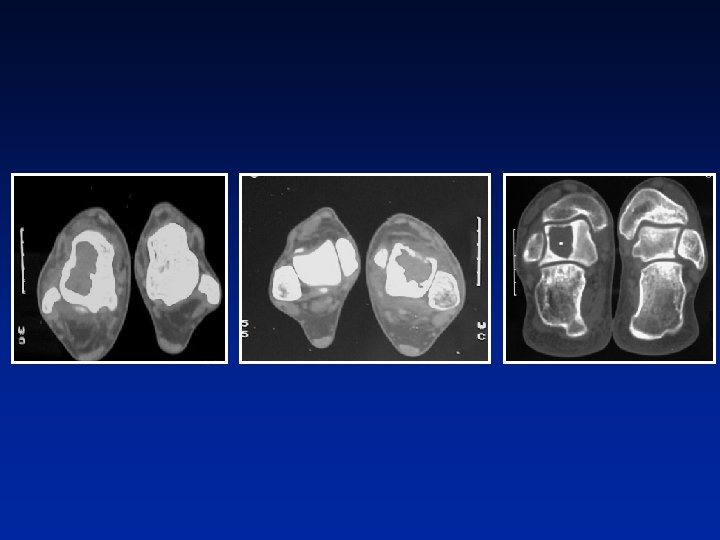

TUMOR DE CELULAS GIGANTES DIAGNOSTICO RADIOLOGICO Destrucción cortical “tumores agresivos” Importancia de la TAC o de la RMN